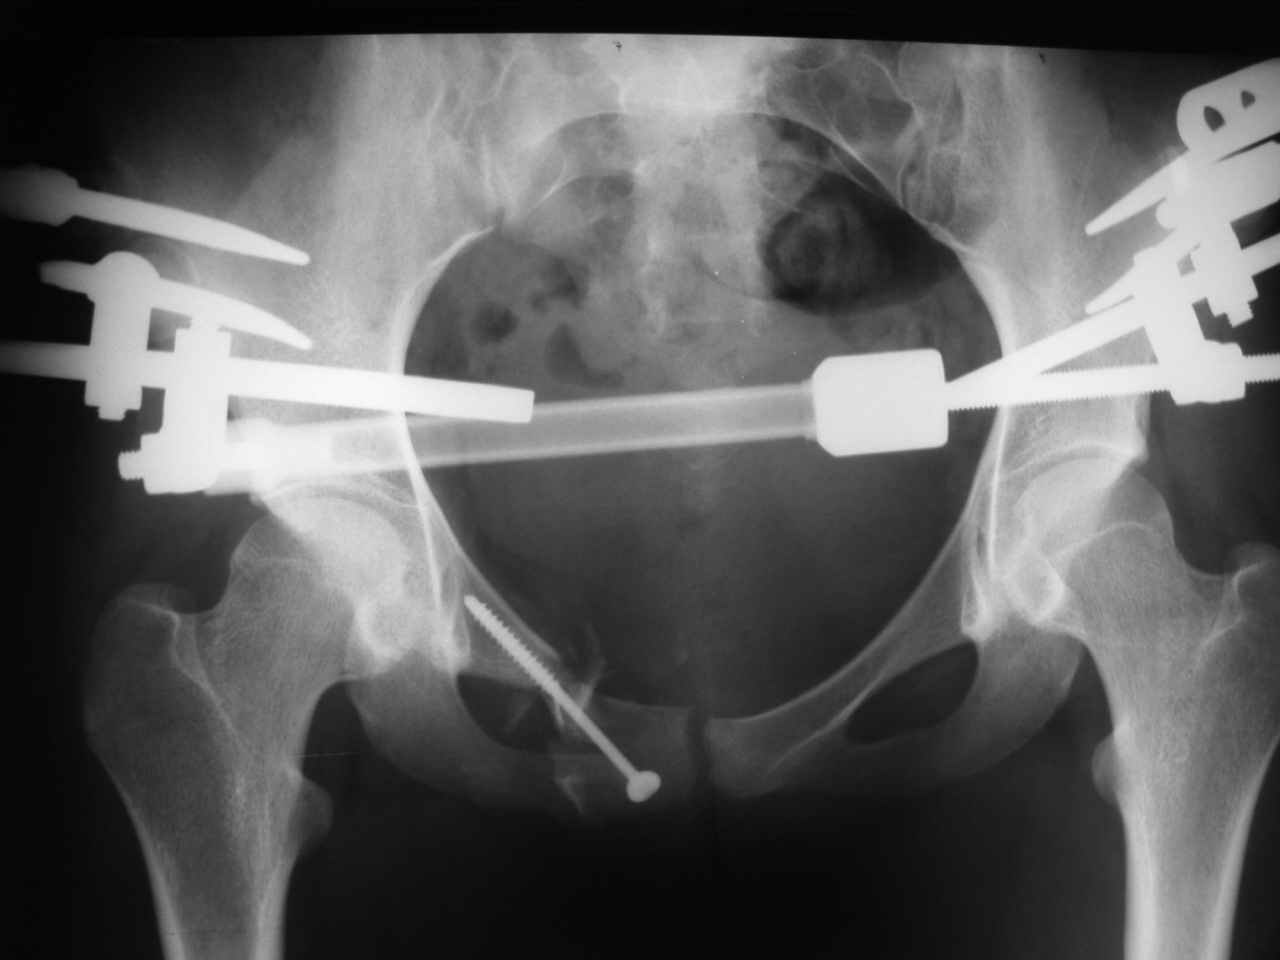

Уважаемые коллеги! К нам поступила молодая девушка 18 лет с оскольчатым переломом лонной и седалищной кости справа, после травмы прошел 1 месяц. Нужно ли вообще оперировать, стоит ли гнаться за анатомией? Или сделать комбинированный остеосинтез?

Надо бы начать с дополнительных проекций (хотя бы inlet), сделать КТ для уточнения повреждения задних отделов таза - виден перелом крестца. Здесь, похоже, ротационно нестабильное повреждение по механизму бокового сжатия. И вообще, Алексей, у тебя же есть экземпляр моей диссертации - читай на ночь ;-)

ЕЧ -Прямая проекция только не дает полной информации о характере повреждений заднего отдела. Судя по механизму травмы, задняя крестцово-подвздошная связка должна пострадать помимо видимого на Рг грамме трансфораминального перелома справа. КТ и инлет проекция были бы полезны.

но ежели собиретесь, то фиксацией переднего отдела только не обойтись: я бы начал с фиксации заднего отдела одним, двумя винтами-стяжками - передний отдел тазадолжен раскрыться и пластина на лонные кости.

В принцине анатомия - функционально обоснованное пространственное расположение образований, составляющих тазовое кольцо. Если внимательно присмотреться даже к этому снимку - можно выявить грубую деформацию, сравнимую со смещением по длине, ширине и под углом диафиза длинной трубчатой кости. Кроме того имеет место импрессионный перелом боковых масс крестца, ротационное смещение правой половины таза, грубое нарушение непрерывности костного остова по лобковой дуге с линейным и ротационным

смещением справа, некорректная установка головки правого бедра с вытекающими последствиями. Так что уж и не знаю надо ли гнаться за анатомией или физиологией или биомеханикой. При переломах бедра и голени этих вопрсов уже не возникает.

Проблема этой девушки не спереди а сзади в поврежденном крестцово-подвздошном сочленении с той же стороны. Судя по снимку есть смещение. Нужно сделать снимки на вход и выход таза (outlet, inlet) и стоит добавить КТ и тогда решить об операции. Судя по снимку девушка нуждается в вправлении и фиксации или артродезе крест-подвзд.